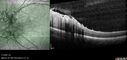

Bullous Retinoschisis - Asymptomatic54 viewsDec 17, 2025

Bullous Retinoschisis - Asymptomatic61 viewsDec 17, 2025

Bullous Retinoschisis - Asymptomatic57 viewsDec 17, 2025